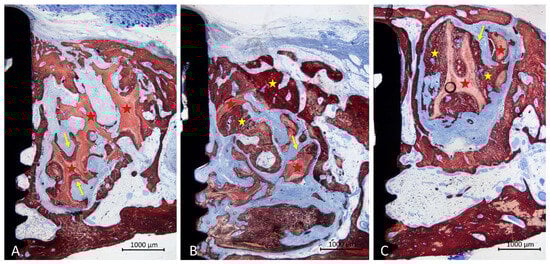

3.2. Descriptive Histological Evaluation